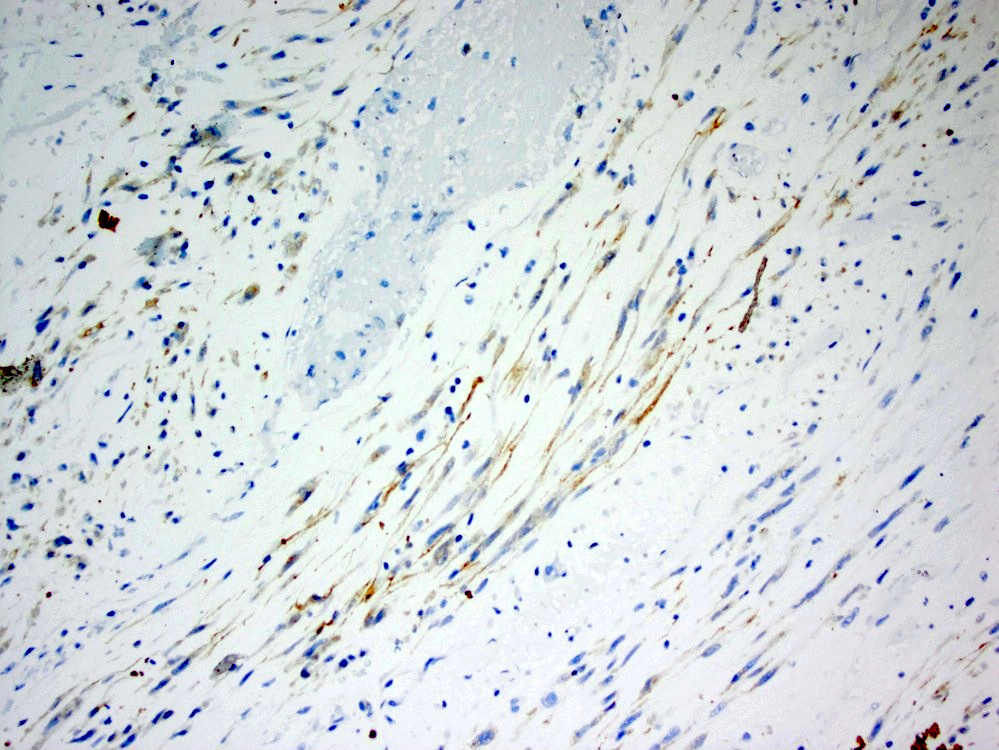

Positive stains

- Desmin, smooth muscle actin; variable cytoplasmic ALK1 (Mod Pathol 2002;15:931)

- Epithelioid inflammatory myofibroblastic sarcoma: nuclear membrane ALK1

- Comment: An immunostain for ALK1 is positive in the tumor.

A young male patient presents with abdominal pain. Imaging reveals a large mesenteric mass, which is resected. An image of the tumor’s histology is seen above. Immunohistochemistry shows ALK1 staining of the nuclear membranes. What molecular abnormality is present in this tumor?

C. t(2;2) RANBP2-ALK translocation. This is an epithelioid inflammatory myofibroblastic sarcoma.